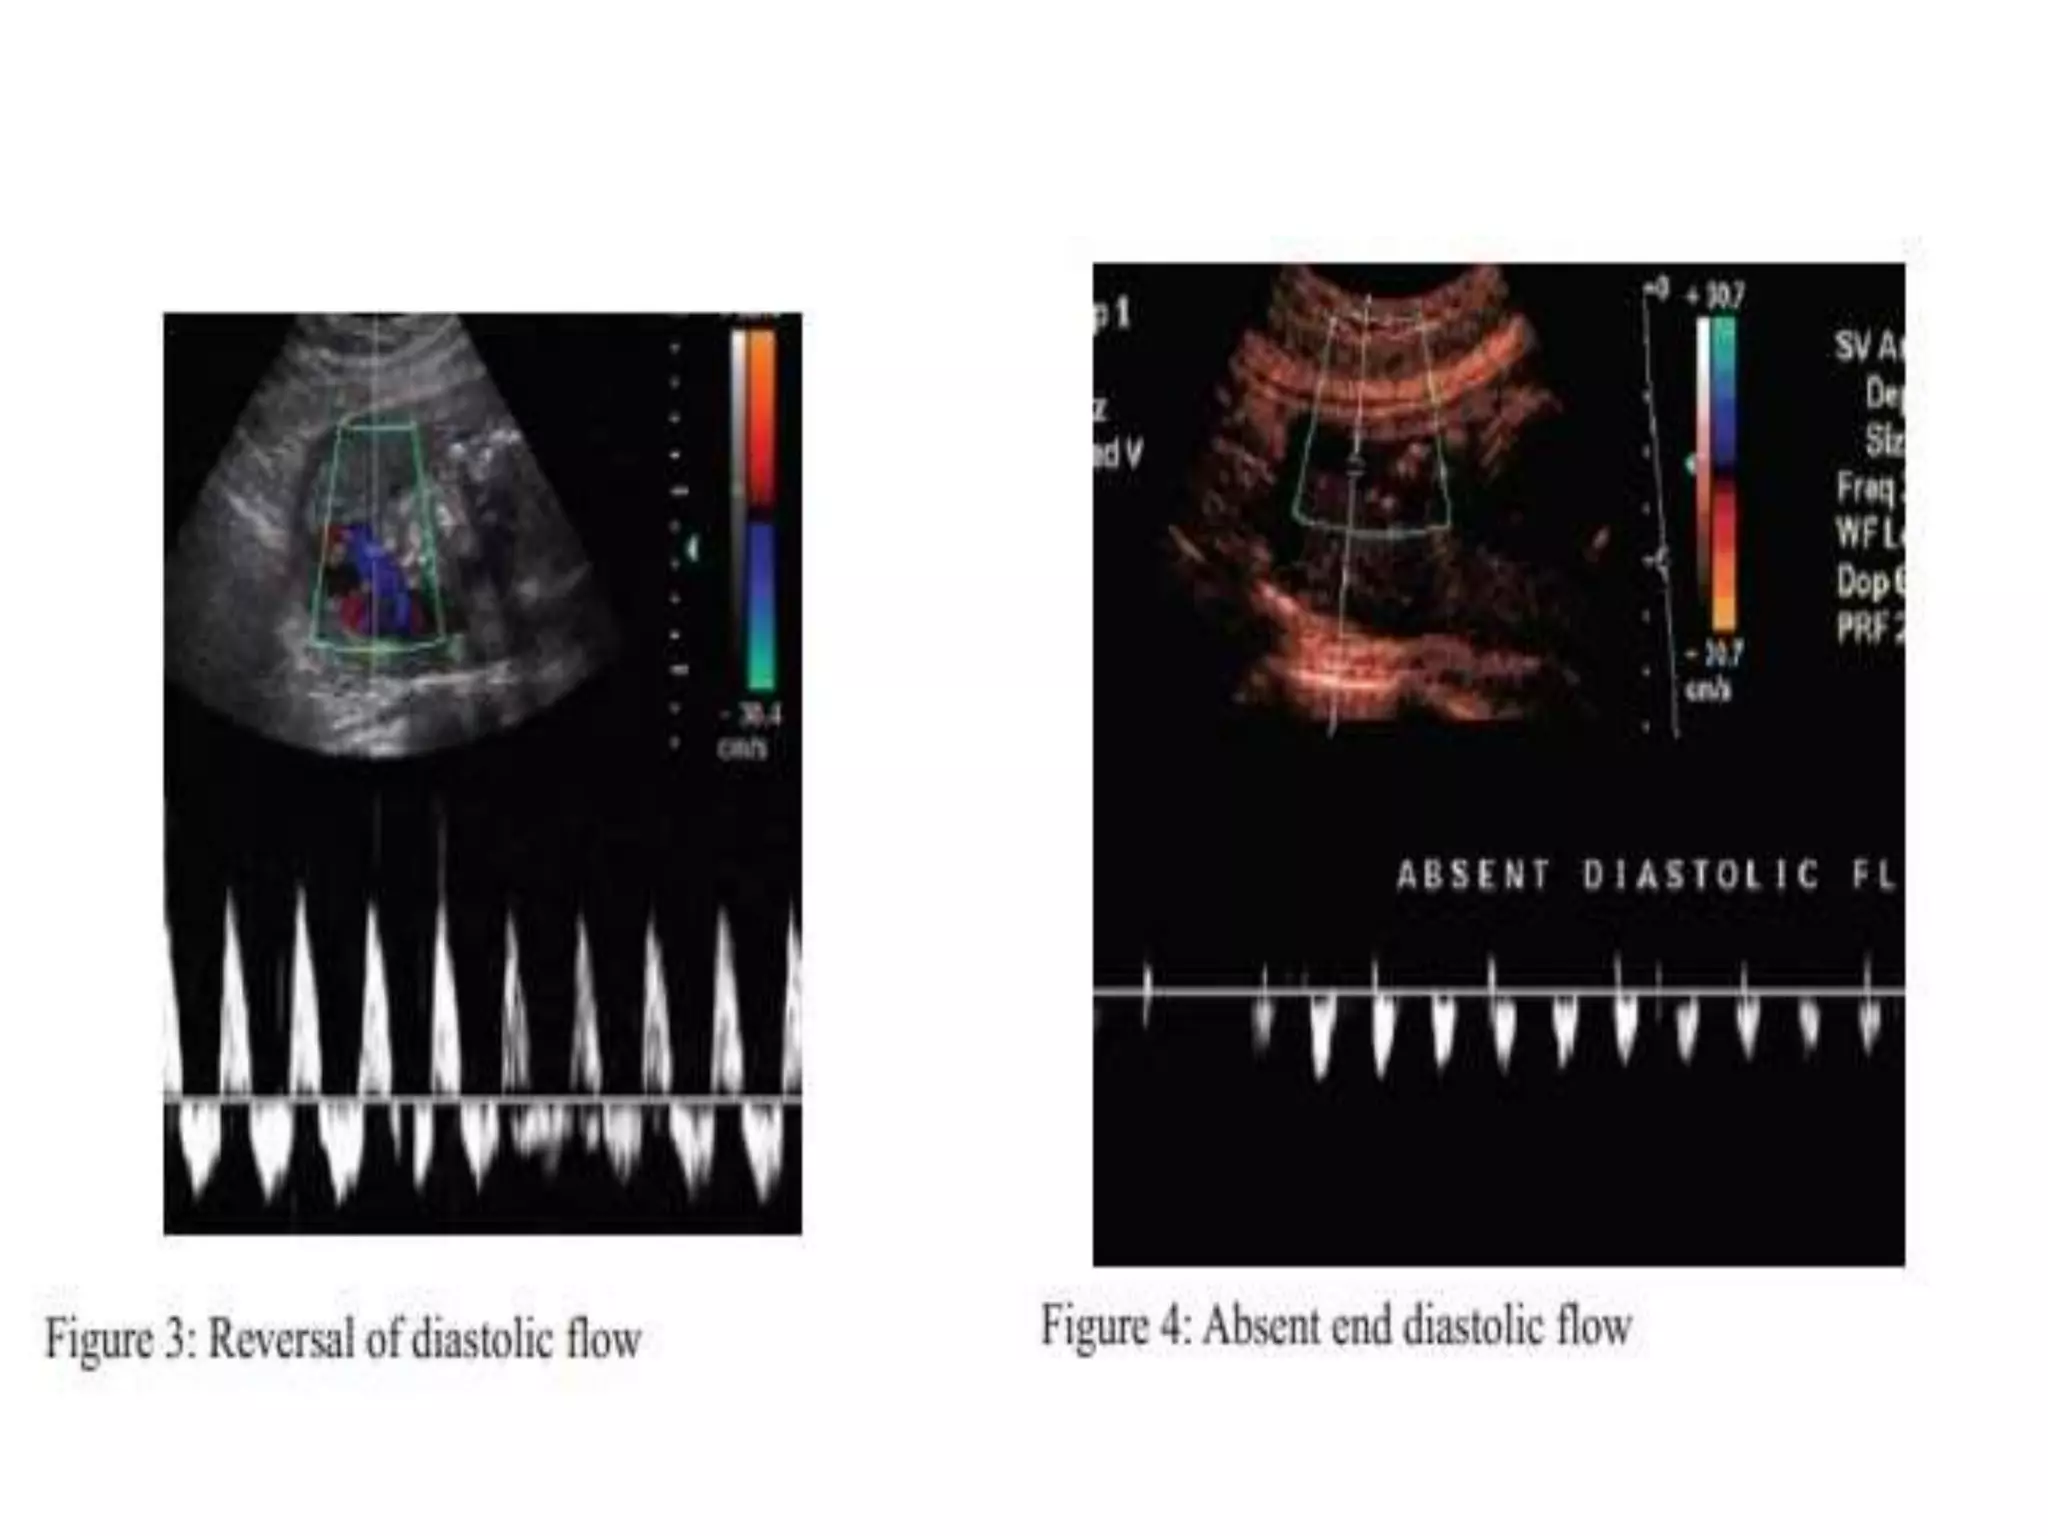

•   in Cases of IUGR there is increase in PI index secondary to

decrease, absence or reversal of end diastolic blood flow.

These changes in wave form indicate increased

placental resistance.

The absent or reversed end diastolic flow strongly

associated with worst fetal outcome(40%.Perinatal deaths).

In milder form of placental insufficiency, diastolic flow is

decreased, but absent or reversal of end diastolic flow may

not develop and fetus is thriving well in utero.

In some IUGR cases fetus maintains the normal diastolic flow

velocity in umbilical artery by altering Cardiac out put in order

to maintain Oxygenation. This suggests that umbilical artery

works as a shunt .

Hence umbilical artery is not a KEY vessel to have a

conclusive evidence of fetal Oxygenation status.

UMBILICAL ARTERY Normal doppler wave form

REVERSAL OF BLOOD FLOW IN UMBILICAL ARTERY

UMBILICAL ARTERY DOPPLER : (a) NORMAL (b) LOSS END-

DIASTOLIC FLOW (c) REVERSED END-DIASTOLIC FLOW